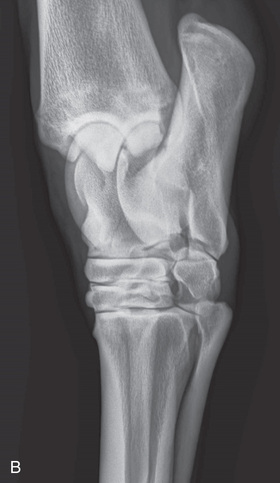

| Stifle | Lateromedial (LM) | Lateral (L) |

| Caudoproximal-craniodistal (CdPr-CrDi) | Caudocranial (CdCr) | |

| Lateral trochlear ridge and medial femoral condyle (stifle) | Caudoproximal 60-degree lateral–craniodistomedial oblique (Cd60L-CrMO) | CdLCrMO |